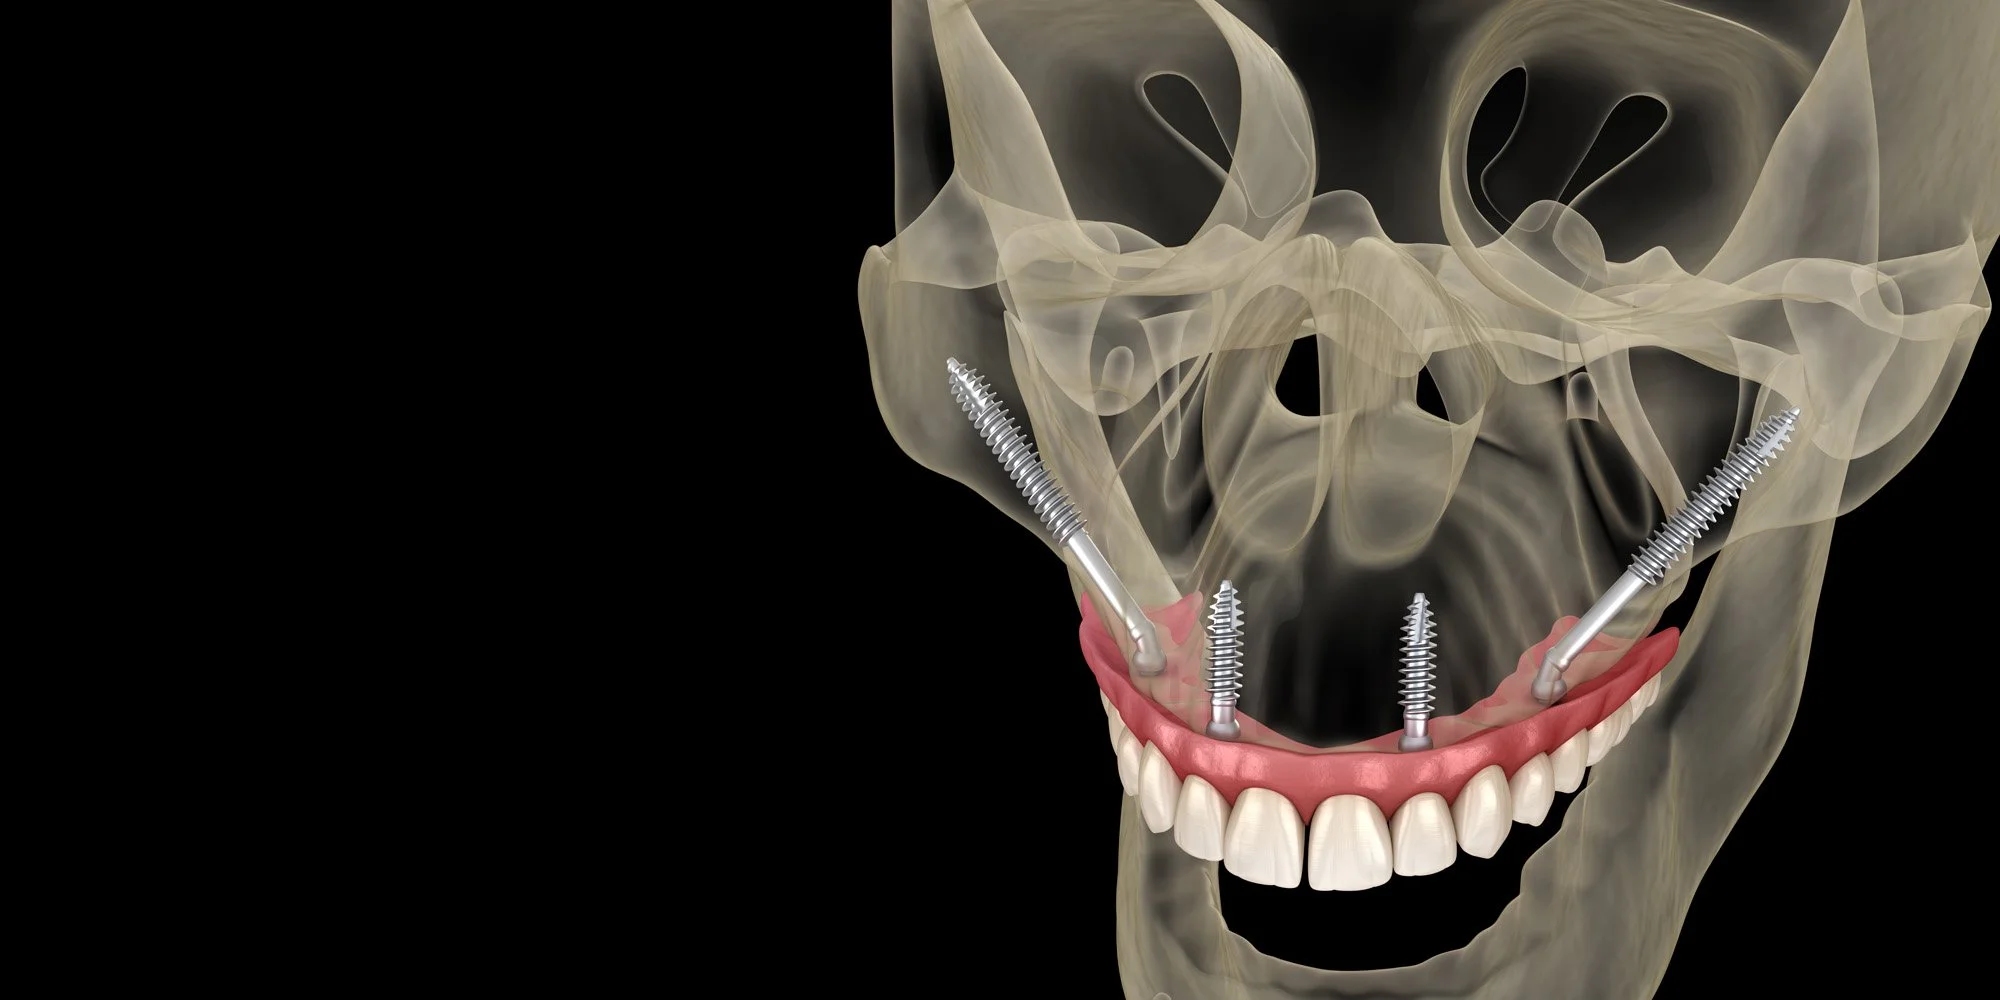

Zigomatik İmplantlar

• Zigomatik implantlar üst çenede arka bölgede kemik erimesine ek ön bölgede de kemik erimesi olduğu durumlarda üst çene kemiğinde hiç kemik kalmadığı durumlarda uygulanan implantlardır.

• Elmacık kemikleri olrak da adlandırılan zigoma kemiklerine uygulanan, normal implantlardan çok daha zun implantlardır.

• Zigoma implantı işlemi genel anestezide full narkoz altında ugyulanır. Hasta işlem esnasında hiçbir sey hatırlamaz.

• Zigoma implantları yapıldıktan 1 hafta sonra sabit dişler takılır ve hemen çiğnemeye başlayabilir.